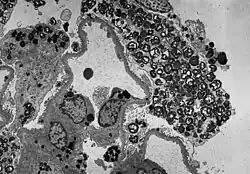

Das am leichtesten zu erkennende Frühsymptom bei Morbus Fabry sind Angiokeratome. Dies sind gutartige rot-violette Hautveränderungen mit leichten Erhebungen. Sie werden typischerweise an Gesäß, Leistenregion, Bauchnabel und Oberschenkel gebildet. Gelegentlich sind auch die Schleimhäute, beispielsweise im Mund, betroffen. In den meisten Fällen handelt es sich bei den Angiokeratomen um kleine oberflächliche Angiome, die durch Schäden des vaskulären Endothels der Haut, verbunden mit Vasodilatationen in der Haut, entstanden sind. Sie nehmen in Anzahl und Größe mit dem Alter zu und können einzeln oder in Gruppen auftreten.[60][64] Neben den Angiomen wurden auch Fälle mit Teleangiektasien[60][62] und subkutanen Ödemen[65] als Ursache der Angiokeratome berichtet.[7]

-

Histologisches Präparat einer mittels Biopsie entnommenen Hautprobe eines Patienten mit Morbus Fabry.

In der lichtmikroskopischen Aufnahme lassen sich die typischen Hautläsionen als kleine oberflächliche Angiome erkennen. -

Fluoreszenzmikroskopaufnahmen eines Gefrierschnittes der Haut eines Morbus-Fabry-Patienten.

Auffällig ist der Mangel an intraepidermalen Nervenfasern und das Vorhandensein von Fasern, die zum subepidermalen Nervenplexus gehören (Pfeile). Die untere Hautprobe stammt dagegen vom Rücken des Patienten. Hier ist die dichte Innervation der Epidermis (Pfeile) auffällig. -